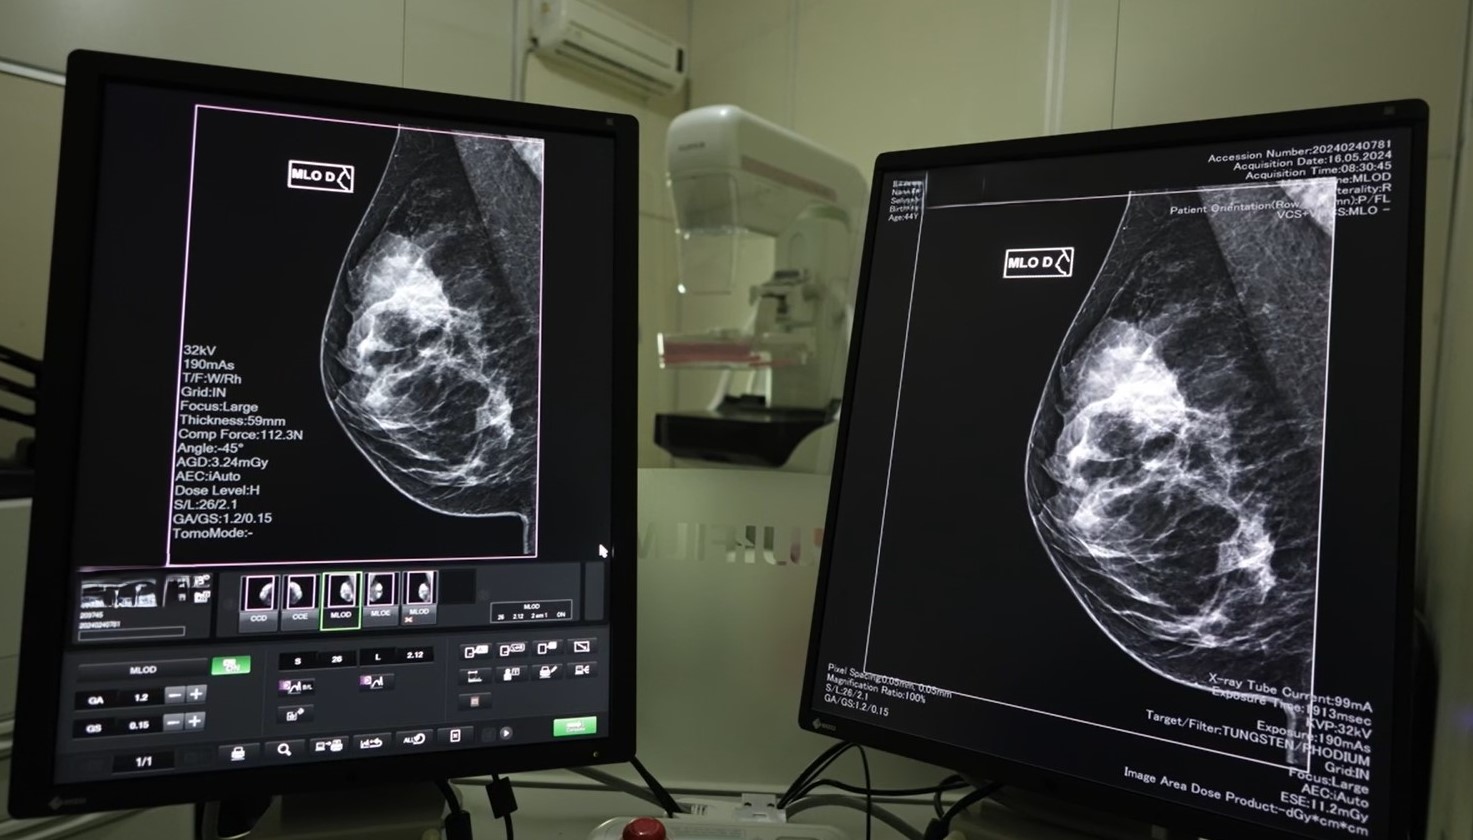

Em 2024, Santa Catarina registrou mais de 2,5 mil novos casos de câncer de mama, e 167,2 mil mamografias foram realizadas pelo SUS. As unidades habilitadas em oncologia também realizaram 613 cirurgias relacionadas à doença no último ano. A detecção precoce é essencial para aumentar as chances de cura, tornando os tratamentos menos invasivos e mais eficazes.

A SES reforça que as mamografias são oferecidas gratuitamente pelo SUS, e qualquer mulher que identificar um nódulo ou sintoma suspeito deve procurar uma Unidade Básica de Saúde (UBS) para atendimento e encaminhamento aos exames necessários. Além da mamografia, o SUS também oferece ultrassonografia e ressonância magnética quando há indicação médica.